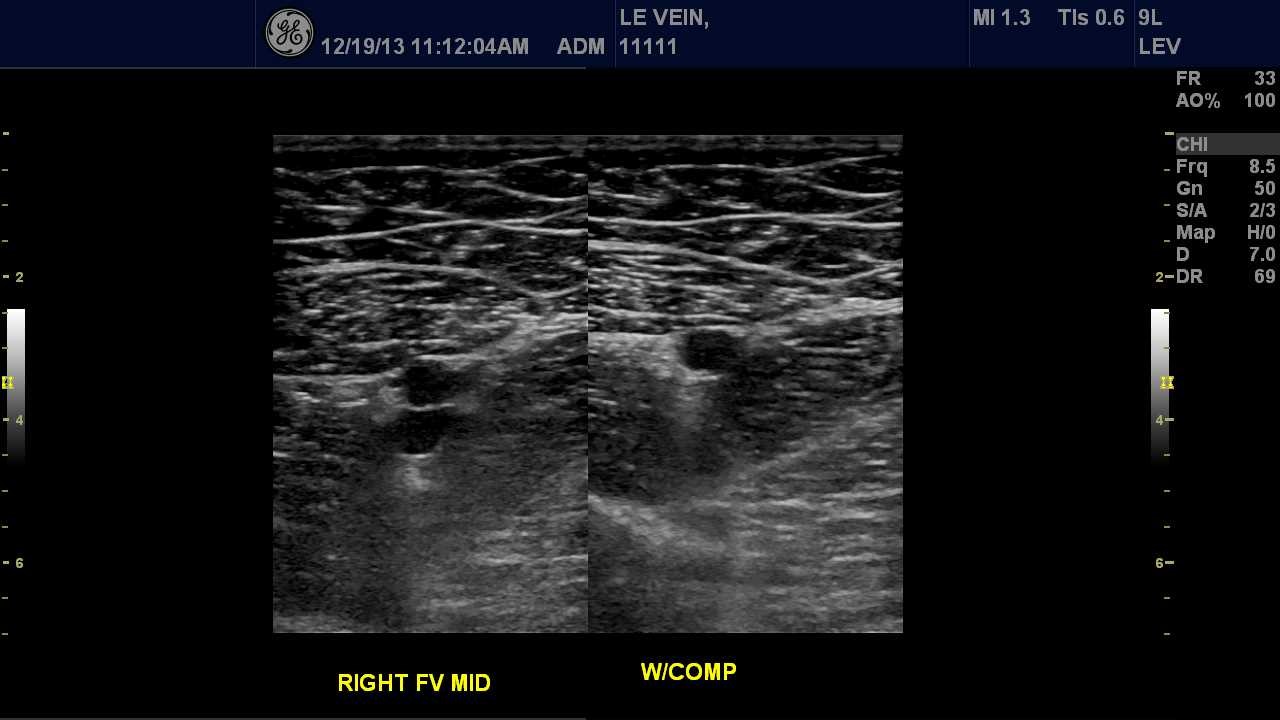

Lower Venous Duplex Examination

When the sonographer assesses the veins in the legs including the external iliac, common femoral, femoral, popliteal, gastrocnemius, posterior tibial, peroneal, greater saphenous and small saphenous veins.

Lower Extremity Vein Ultrasound Image

Depending on the type of examination or test being performed, the sonographer may have you change into a gown and remove your jewelry or watch if necessary. While laying on your back, a trained vascular sonographer or technologist will perform the examination by applying a water-soluble gel to the skin and placing a transducer on your skin. Depending on the exam, the sonographer might ask you to reposition onto your side or stomach, hold your breath or perform a Valsalva maneuver (hold your breath while bearing down on your lower pelvic muscles). If the examination is a venous duplex checking for blood clots, the sonographer will apply pressure to the skin making sure the vein collapses. This may be uncomfortable, but the sonographer is performing the exam so your doctor can decide further action. The diagnostic testing may take 15 to 60 minutes to perform.